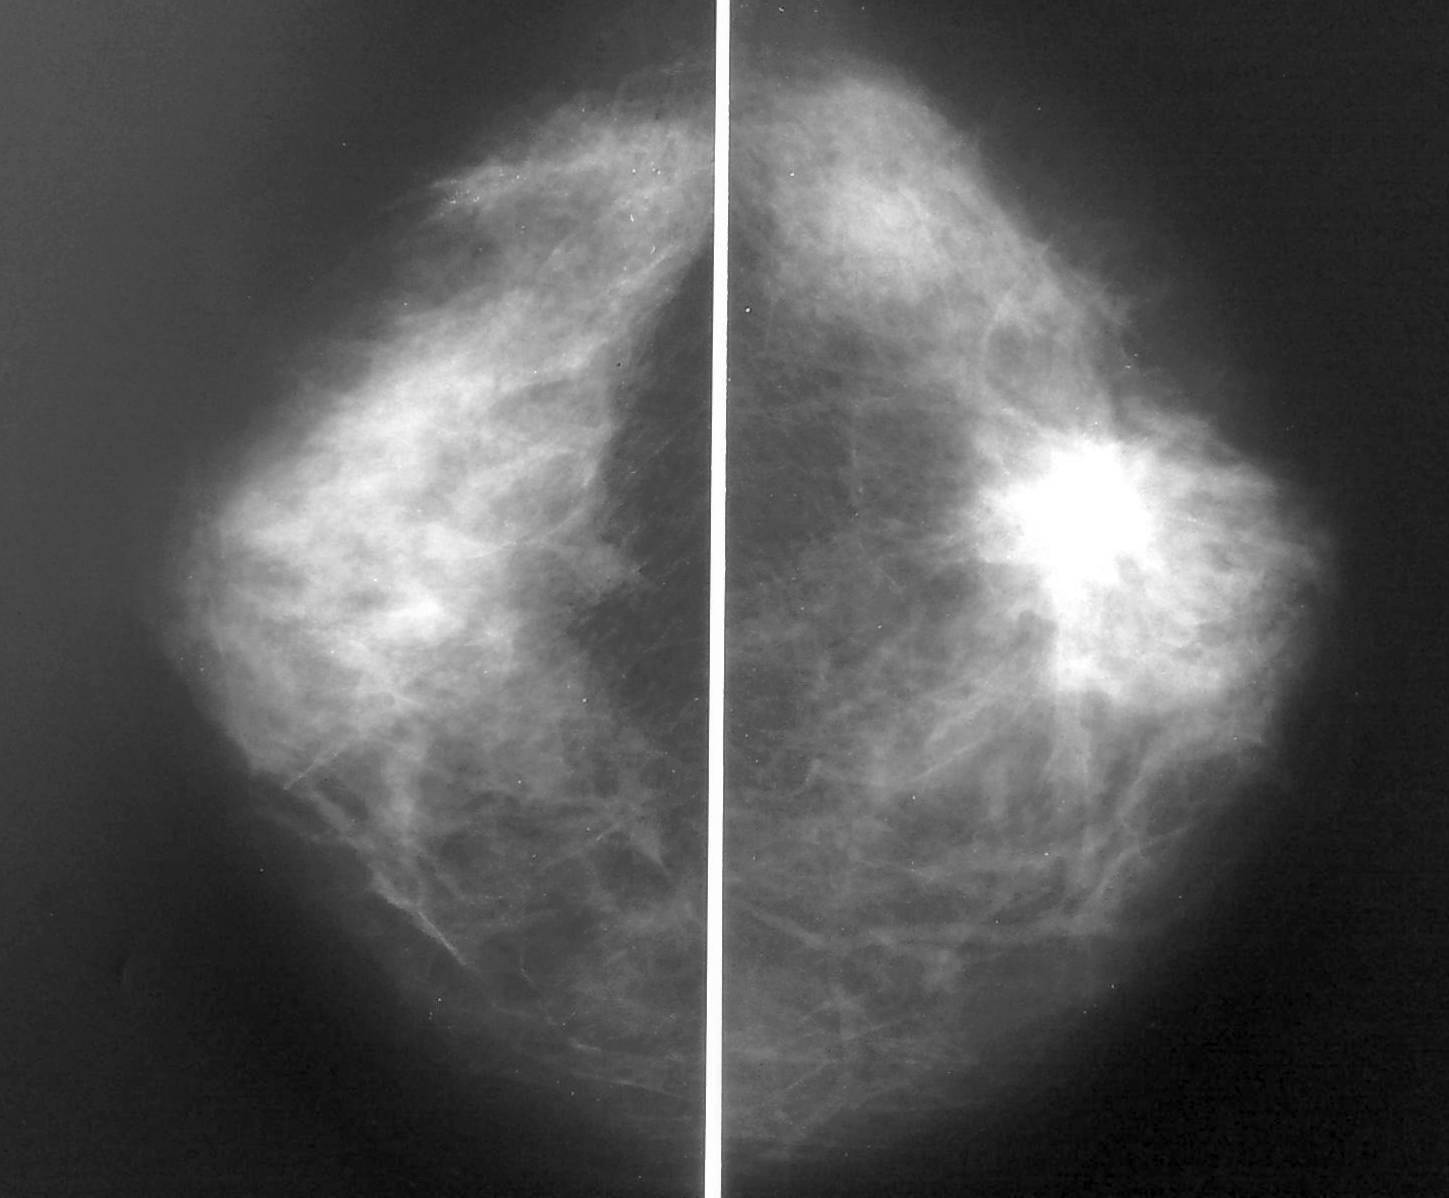

Фиброаденома молочной железы - доброкачественное образование, которое часто встречается у женщин. Оно может быть обнаружено при помощи различных методов диагностики, включая маммографию. Ниже представлены фотографии, помогающие понять, как выглядит данное заболевание.

Опухоль на снимке маммографии

Злокачественные опухоли молочных желез

Маммография и ее роль в диагностике фиброаденомы молочной железы

Маммография - это рентгенологическое исследование молочных желез. Оно позволяет выявить различные изменения в тканях, включая фиброаденому. На маммограммах можно увидеть структурные особенности опухоли и отследить ее динамику во времени.